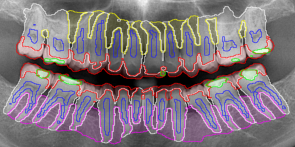

3.3 Qualitative Results

Evaluating the method qualitatively, as seen in Figure 7, all models exhibit overall well performing predictions at most segmentation tasks, but with occasional poor performance for certain edge case samples. Additionally, while all models perform well at detecting the majority of the classes in each image, the quality of the predicted edges are often noisy. Generally, HRNet-H performed best followed by UNet-H, HRNet and UNet. Non hierarchical versions of HRNet and UNet often exhibit noisier predictions when compared to their hierarchical counterparts.

Refer to caption

(a) UNet Image 043

(b) UNet Image 112

(c) UNet Image 189

(d) UNet-H Image 043

(e) UNet-H Image 112

(f) UNet-H Image 189

(g) HRNet Image 043

(h) HRNet Image 112

(i) HRNet Image 189

(j) HRNet-H Image 043

(k) HRNet-H Image 112

(l) HRNet-H Image 189

(m) Target Image 043

(n) Target Image 112

(o) Target Image 189

Figure 7: Figure containing images with overlaid predictions and targets, for each model. Classes include: Upper Alveolar Bone (yellow), Lower Alveolar Bone (pink), Pulp (dark blue), Dentin (white), Enamel (red) and Composite (green).

A common false positive prediction present in non hierarchical versions is a large number of independent floating predictions, such as in Figure 7(a), 7(c) and 7(i), there are spots of dentin predictions away from the tooth within the alveolar bone. These false predictions are not present in the hierarchical versions, as each fine grained child prediction is constrained by its parent class, ensuring that detailed features in the dentin class is only detected where the broader easily detected tooth class is also present. However, occasionally this behaviour can still exist within the bounds of the parent class, such as within Figure 7(e) which contain enamel predictions at the end of a root.

All models produce predictions with a large number of small split object for classes with unclear boundaries, such as pulp and tooth predictions in Figure 7(b) and 7(l). Although, this prediction behaviour is more prevalent in the non hierarchical versions, with HRNet-H producing the least of these errors.

Image 112 depicts an example of the average performance for each model. However, as seen in image 189, certain edge cases such as missing teeth, impacted third molars, or extensive reconstructive work, can cause the models to perform poorly for those samples. However, even though all models perform poorly on these edge case samples, both hierarchical versions generally perform better than their non hierarchical counterparts. All models generally perform well at alveolar bone segmentation, but their performance is directly determined by the predicted quality of the other nearby classes. Dentin predictions that have an over predicted area, like in Figure 7(a) and 7(i), reduce the performance of the alveolar bone classes. Although, some models also struggle to detect full alveolar bone areas that contain missing teeth, as seen in Figure 7(f).

Hierarchical versions of both models exhibit higher quality predictions for almost all cases. While quantitative gain is relatively mediocre, qualitative gain is heavily improved as they contain small improvements with much more cohesive predictions, increasing the clinical significance of the hierarchical models.